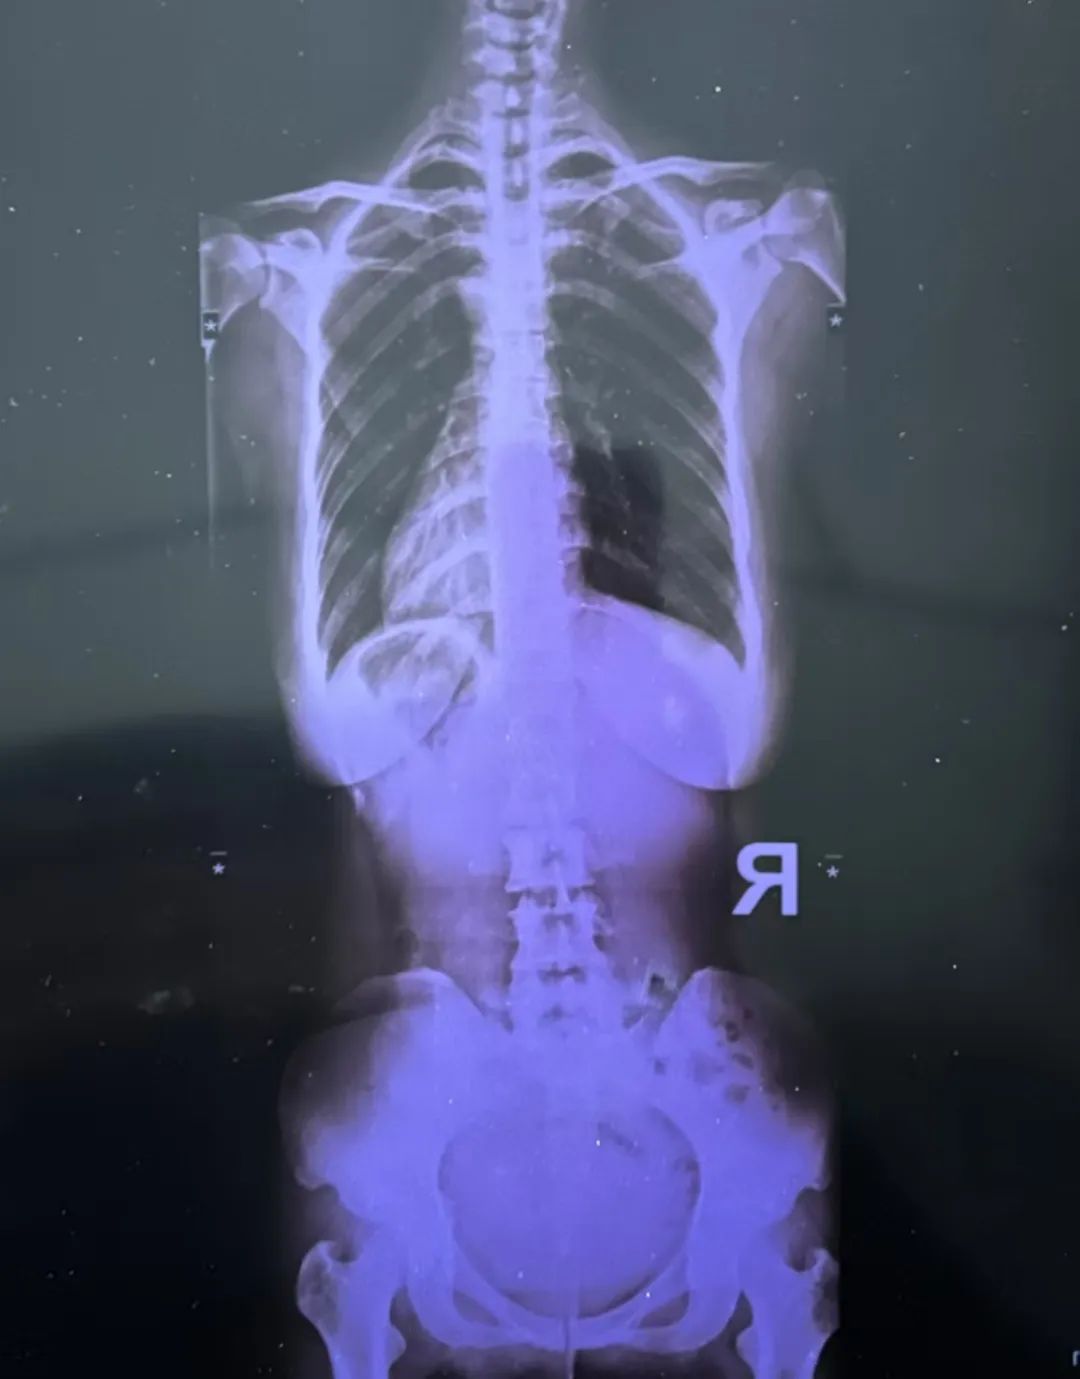

最近又疼起來嚴重影響正常生活,她前往醫(yī)院就診,結(jié)果查出了脊柱側(cè)彎11°,骨盆旋移,骶髂關(guān)節(jié)半脫位,由于這些導致頸肩,后背,腰部肌群代償出現(xiàn)問題,從而出現(xiàn)腰痛,后背痛,肩膀痛!

蘇鴻凱醫(yī)生根據(jù)王女士的具體情況,為王女士制定針對性治療方案,在治療中采用正骨手法復(fù)位,在配合結(jié)構(gòu)針法治療,來調(diào)節(jié)肌肉功能使恢復(fù)平衡。